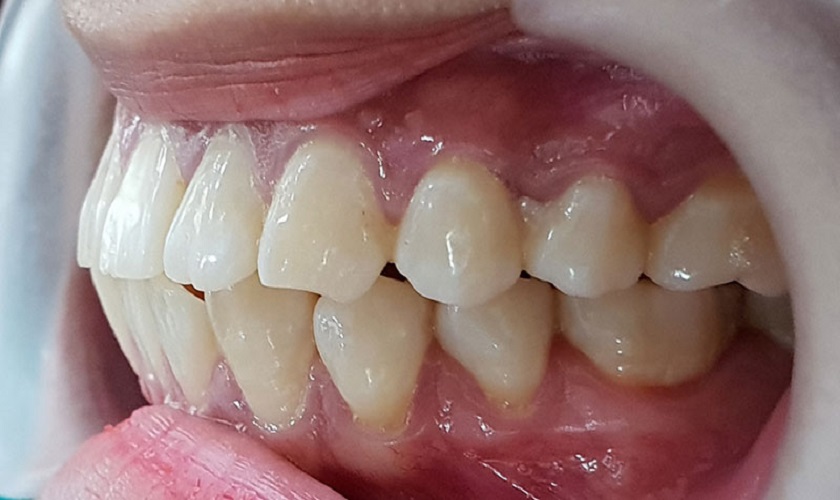

Hiện tượng hô do răng

Hô do răng là tình trạng hô xuất phát từ nguyên nhân răng mọc không đúng vị trí hoặc do các răng cửa phát triển với kích lớn hơn bình thường làm chúng bị chìa ra ngoài ít hoặc nhiều. Khi nhìn bằng mắt thường sẽ thấy các răng trên cung hàm không mọc song song nhau theo hướng thẳng đứng mà sẽ mọc chìa ra ngoài. Lúc này, cung răng ở hàm trên bị hẹp vào trong nên hiện tượng hô răng lộ ra rõ rệt.